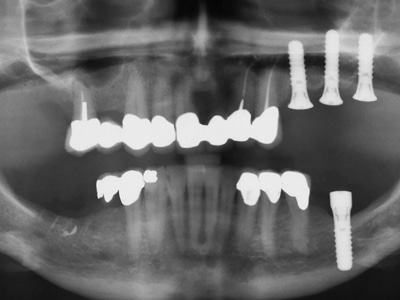

Risk Factors in Implant Dentistry: Operator Related Risk Factors

To view figures, click on figure mentions throughout the article. This article is the fourth in a series by the author submitted to, and published exclusively by Oral Health. The first article of the series was published in the August 2015 issue with the title: Surgical Risk Factors in Implant Dentistry: Influence on Failures and … Read more